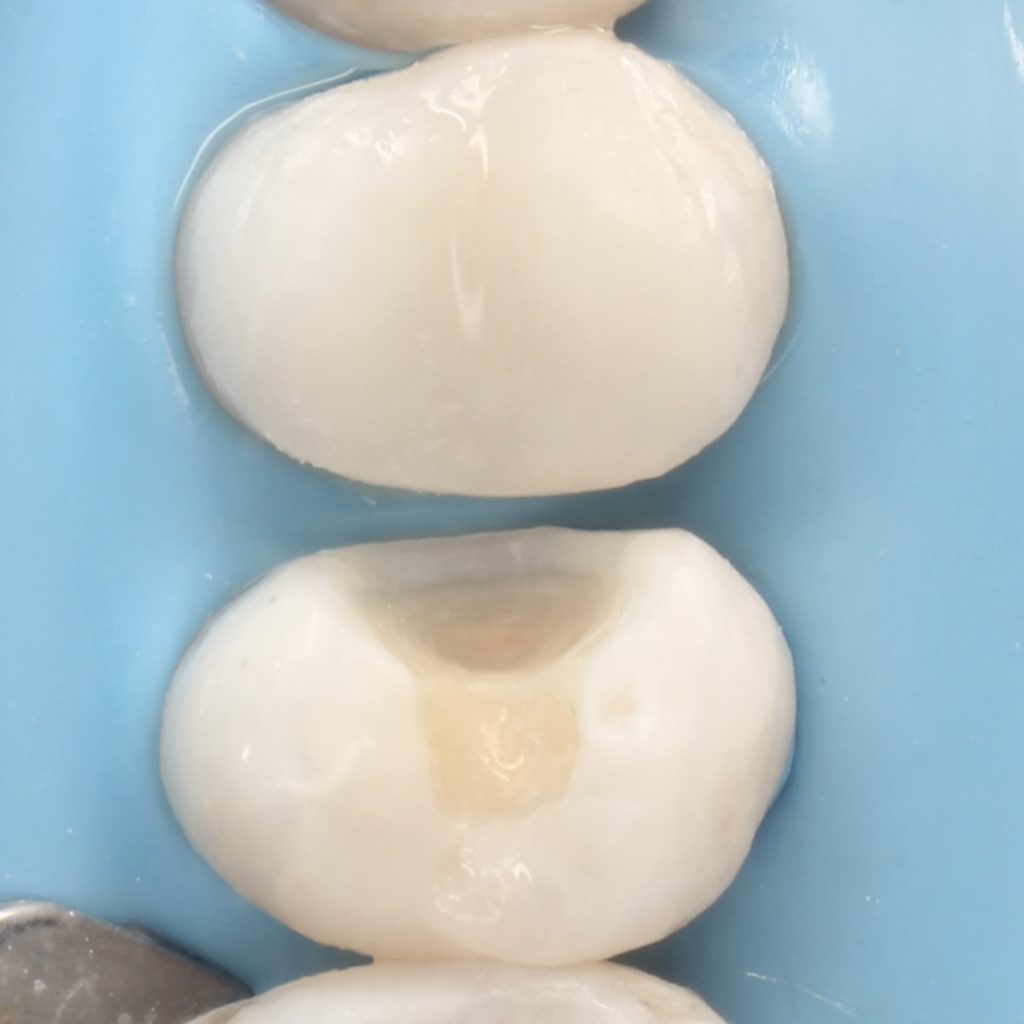

A 22 years old patient came to the clinic suffering from severe spontaneous pain. The diagnosis was acute irreversible pulpitis. The use of CDD is crucial here to ensure the CRE. After finishing endodontic treatment we used polyethylene fibers to enhance the bond strength and the strength of the tooth. Then the use of glass fibers (ever X composite) as a dentin replacement material before the final layer. After finishing. Polishing protocol with eve twist was done to gain the final polish